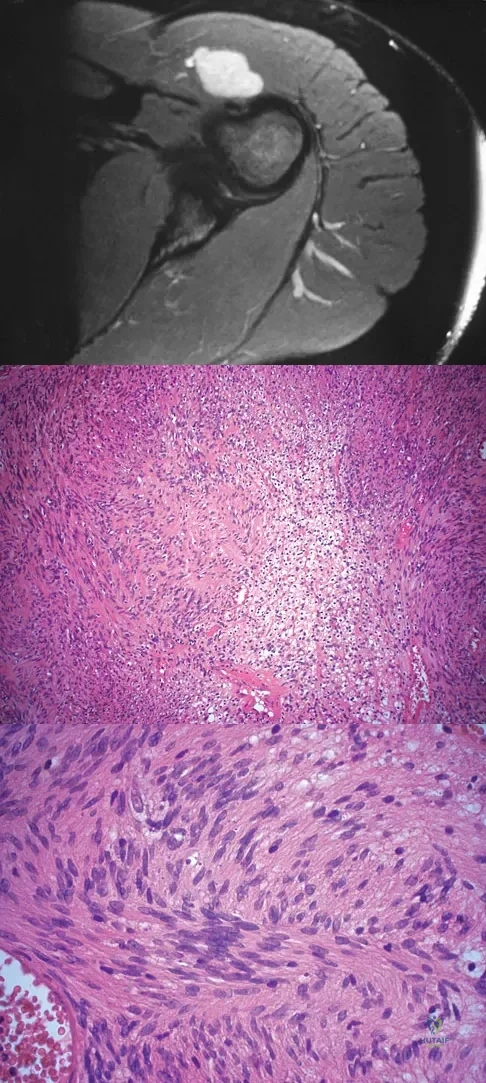

A 28-year-old woman has left shoulder pain and a tender soft-tissue mass. Based on the MRI scan and biopsy specimens shown in Figures 74a through 74c, what is the most likely diagnosis?